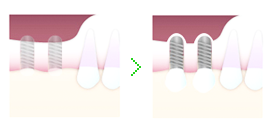

ソケットリフト法

上顎の骨の高さが足りないときに行う手術法です。上顎の鼻周辺には、鼻の穴につながっている上顎洞という大きな穴があります。インプラントがこの上顎洞に突き出てしまわないよう、骨の高さを増大させる必要があります。

上顎の骨の高さが足りないときに行う手術法です。上顎の鼻周辺には、鼻の穴につながっている上顎洞という大きな穴があります。インプラントがこの上顎洞に突き出てしまわないよう、骨の高さを増大させる必要があります。

ソケットリフト法では専用器具で骨を押し上げ、そこに人工骨やご自身の骨を移植することで高さを確保し、インプラントを埋入します。